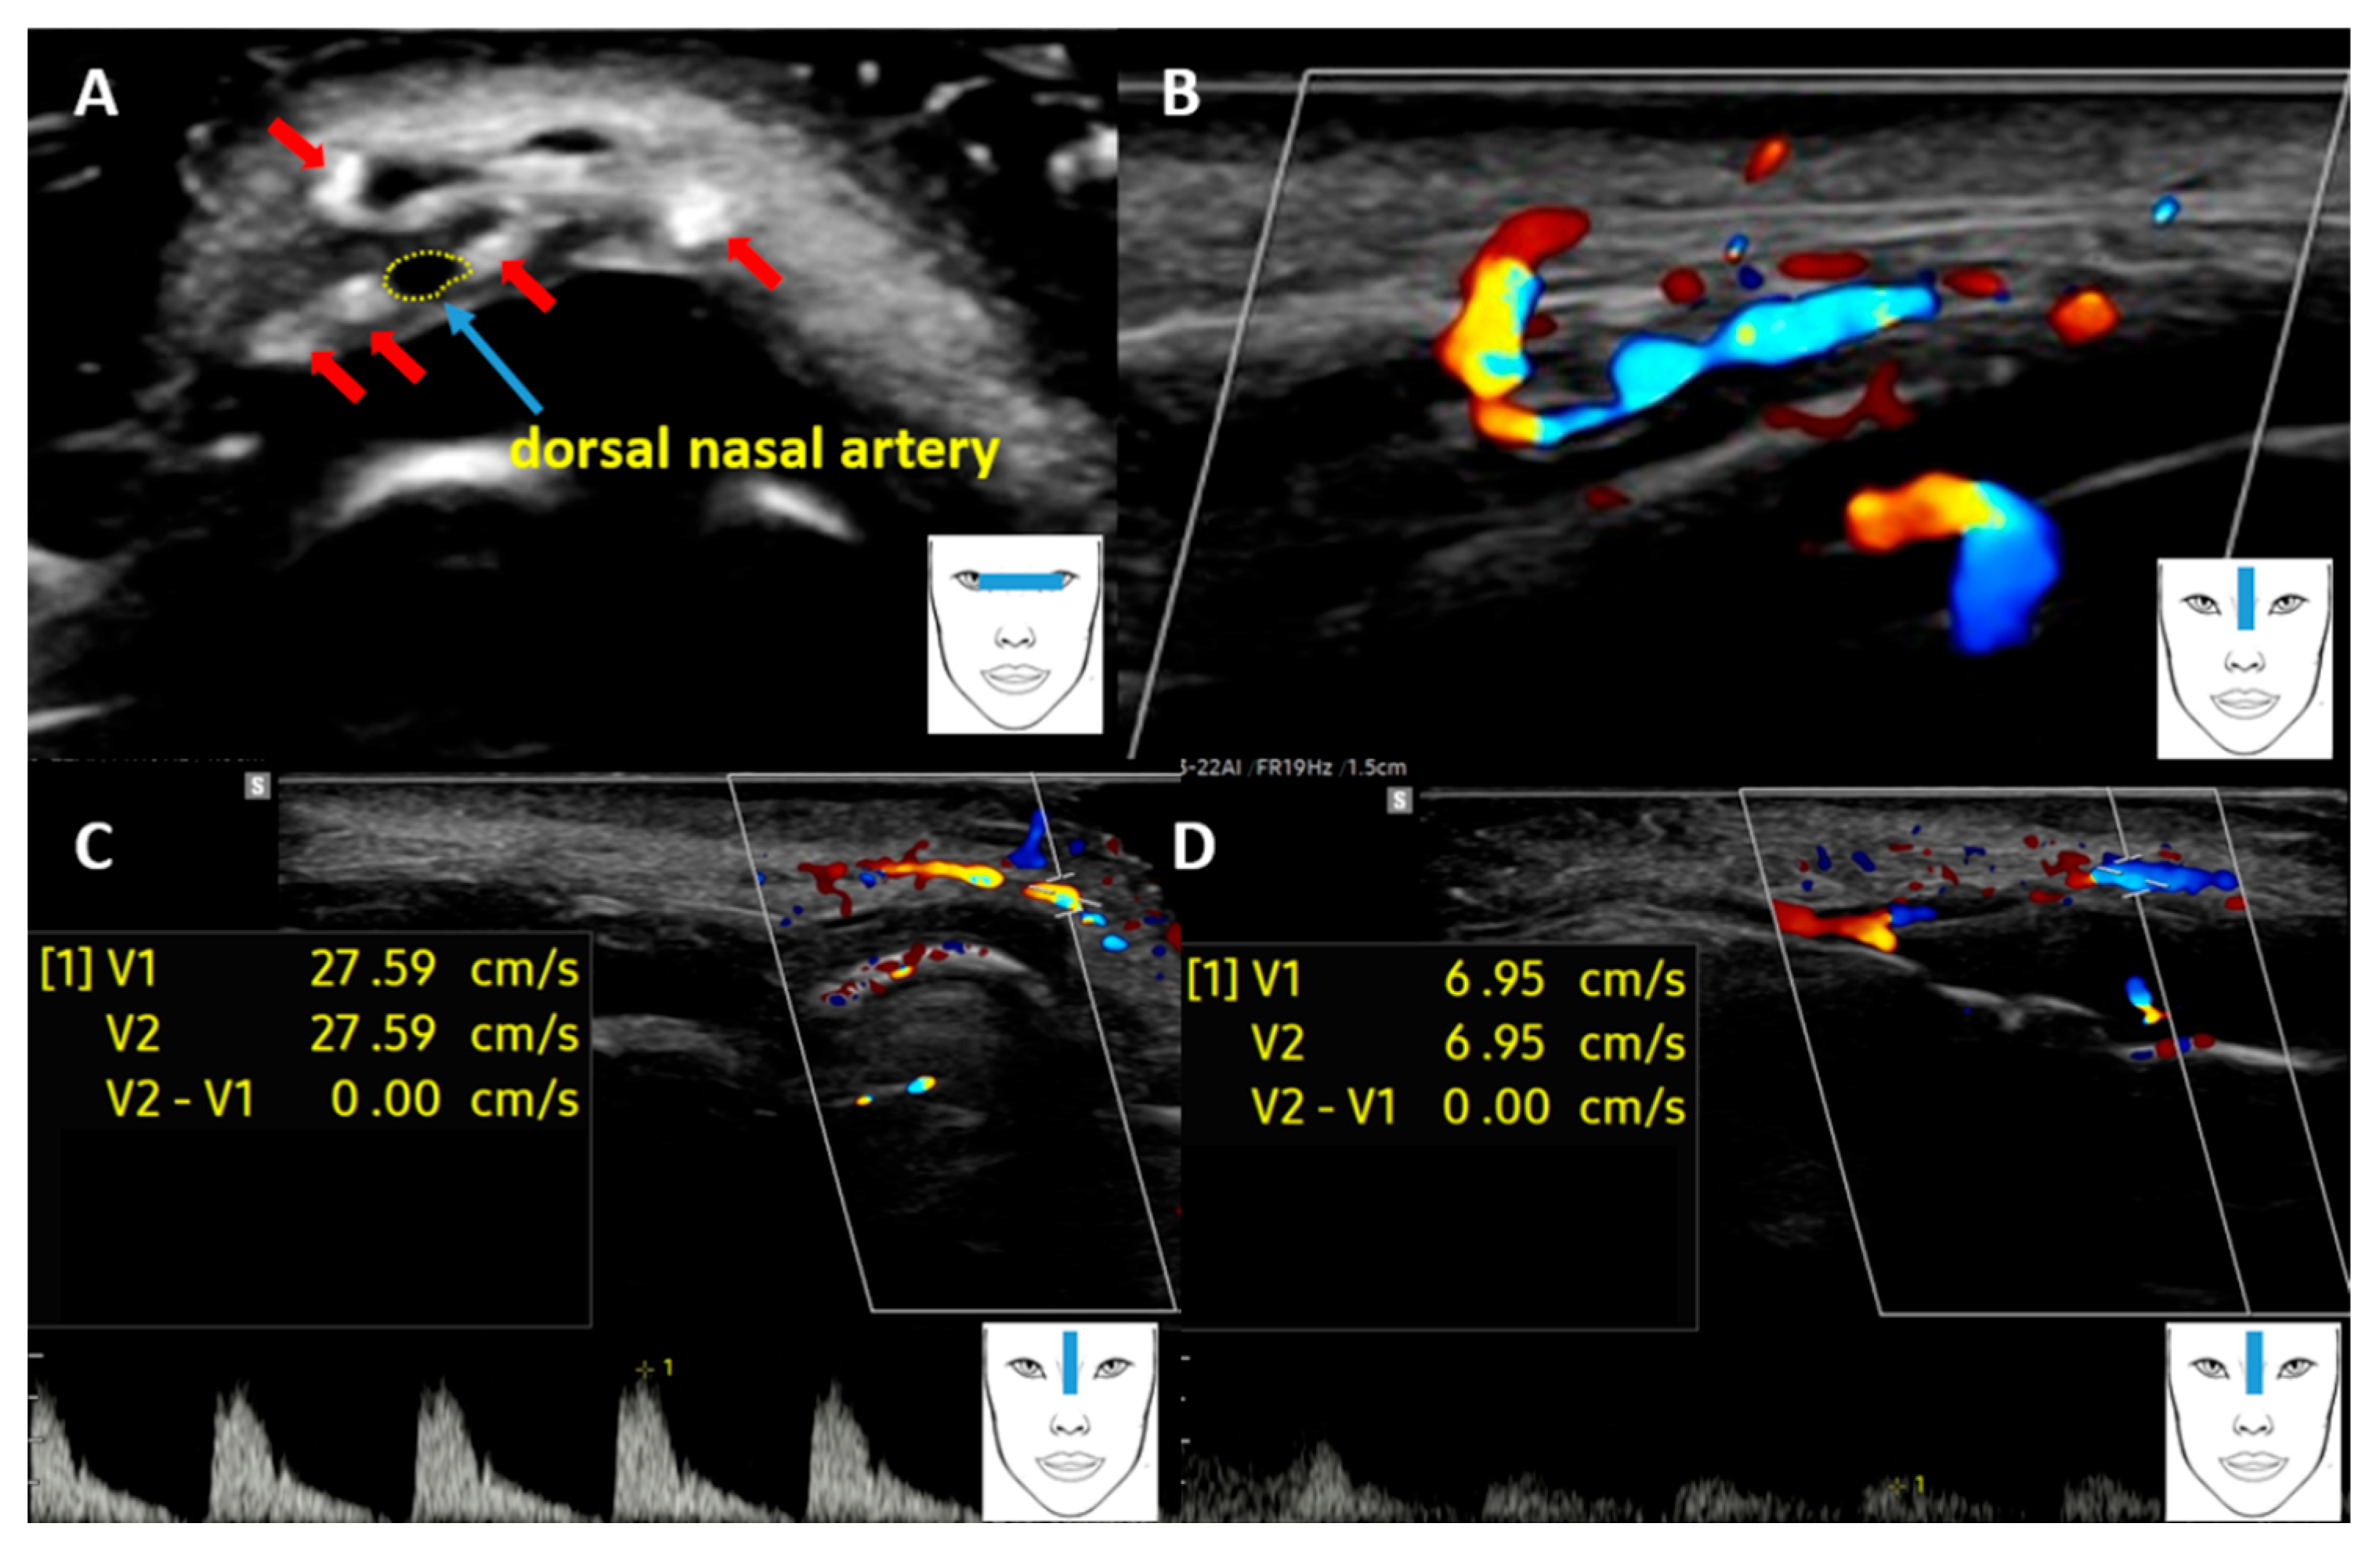

The Usefulness of High-Frequency Ultrasound in Assessing Complications After Minimally Invasive Aesthetic Medicine Procedures, Using the Example of Assessing Blood Flow in the Dorsal Artery of the Nose

Mlosek, R.K. The Usefulness of High-Frequency Ultrasound in Assessing Complications After Minimally Invasive Aesthetic Medicine Procedures, Using the Example of Assessing Blood Flow in the Dorsal Artery of the Nose. Diagnostics 2026, 16, 271. https://doi.org/10.3390/diagnostics16020271